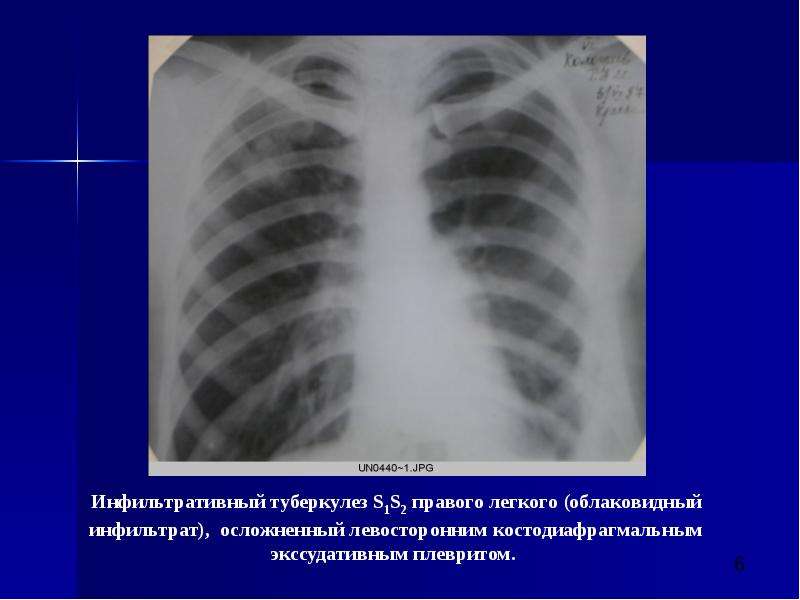

Очаговый и инфильтративный туберкулез презентация - 94 фото